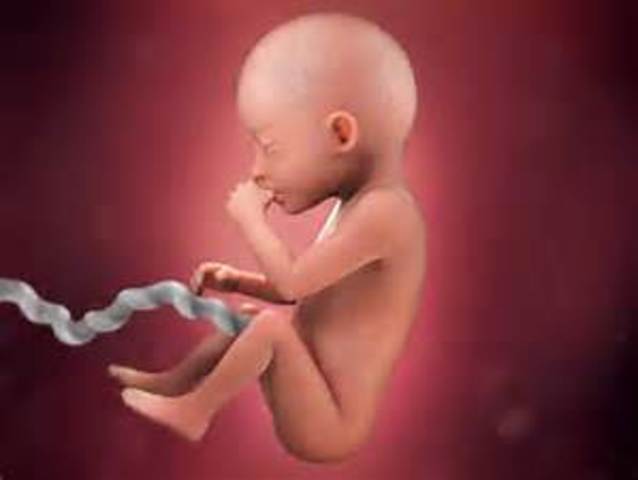

By week eleven, the baby has begun developing ears, toes, an upper lip, and twenty teeth. Also during this week the genitals of the baby have begun to develop.

• Week 12

Week 12

By week twelve,the baby's facial profile, brain, and vocal cords are fully developed. Also by this week you'll be able to hear your baby's heartbeat.